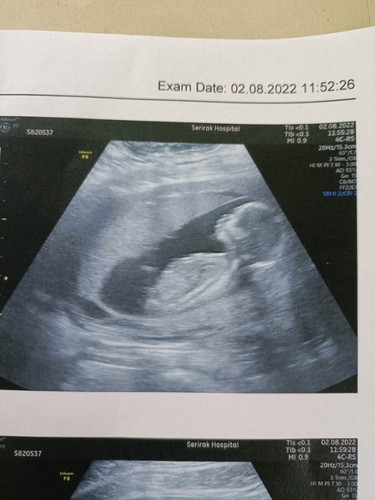

ช่วงท้อง3เดือนแรก ก่อนตรวจเจอแฟนทักว่าหน้าดูดำลงนะ หลังตรวจเจอก็เริ่มแพ้ท้องช่วงเย็นจะกินอะไรไม่ได้เลยอ้วกออกหมด (ท้องแรกลูกสาวไม่เป็นไรเลยหน้าผ่องคนทักว่าลูกสาวเยอะ) ผดเริ่มขึ้นหน้า คนทักว่าลูกชายเกือบทั้งหมดมีไม่ถึง5คนบอกลูกสาว แนบรูปซาวด์ล่าสุดตอน15วีคมาให้ค่ะ เค้าบอกเด็กตัวโตน่าจะได้ผู้ชายกัน ทุกคนคิดว่าไงคะ #ทีมมกรา66